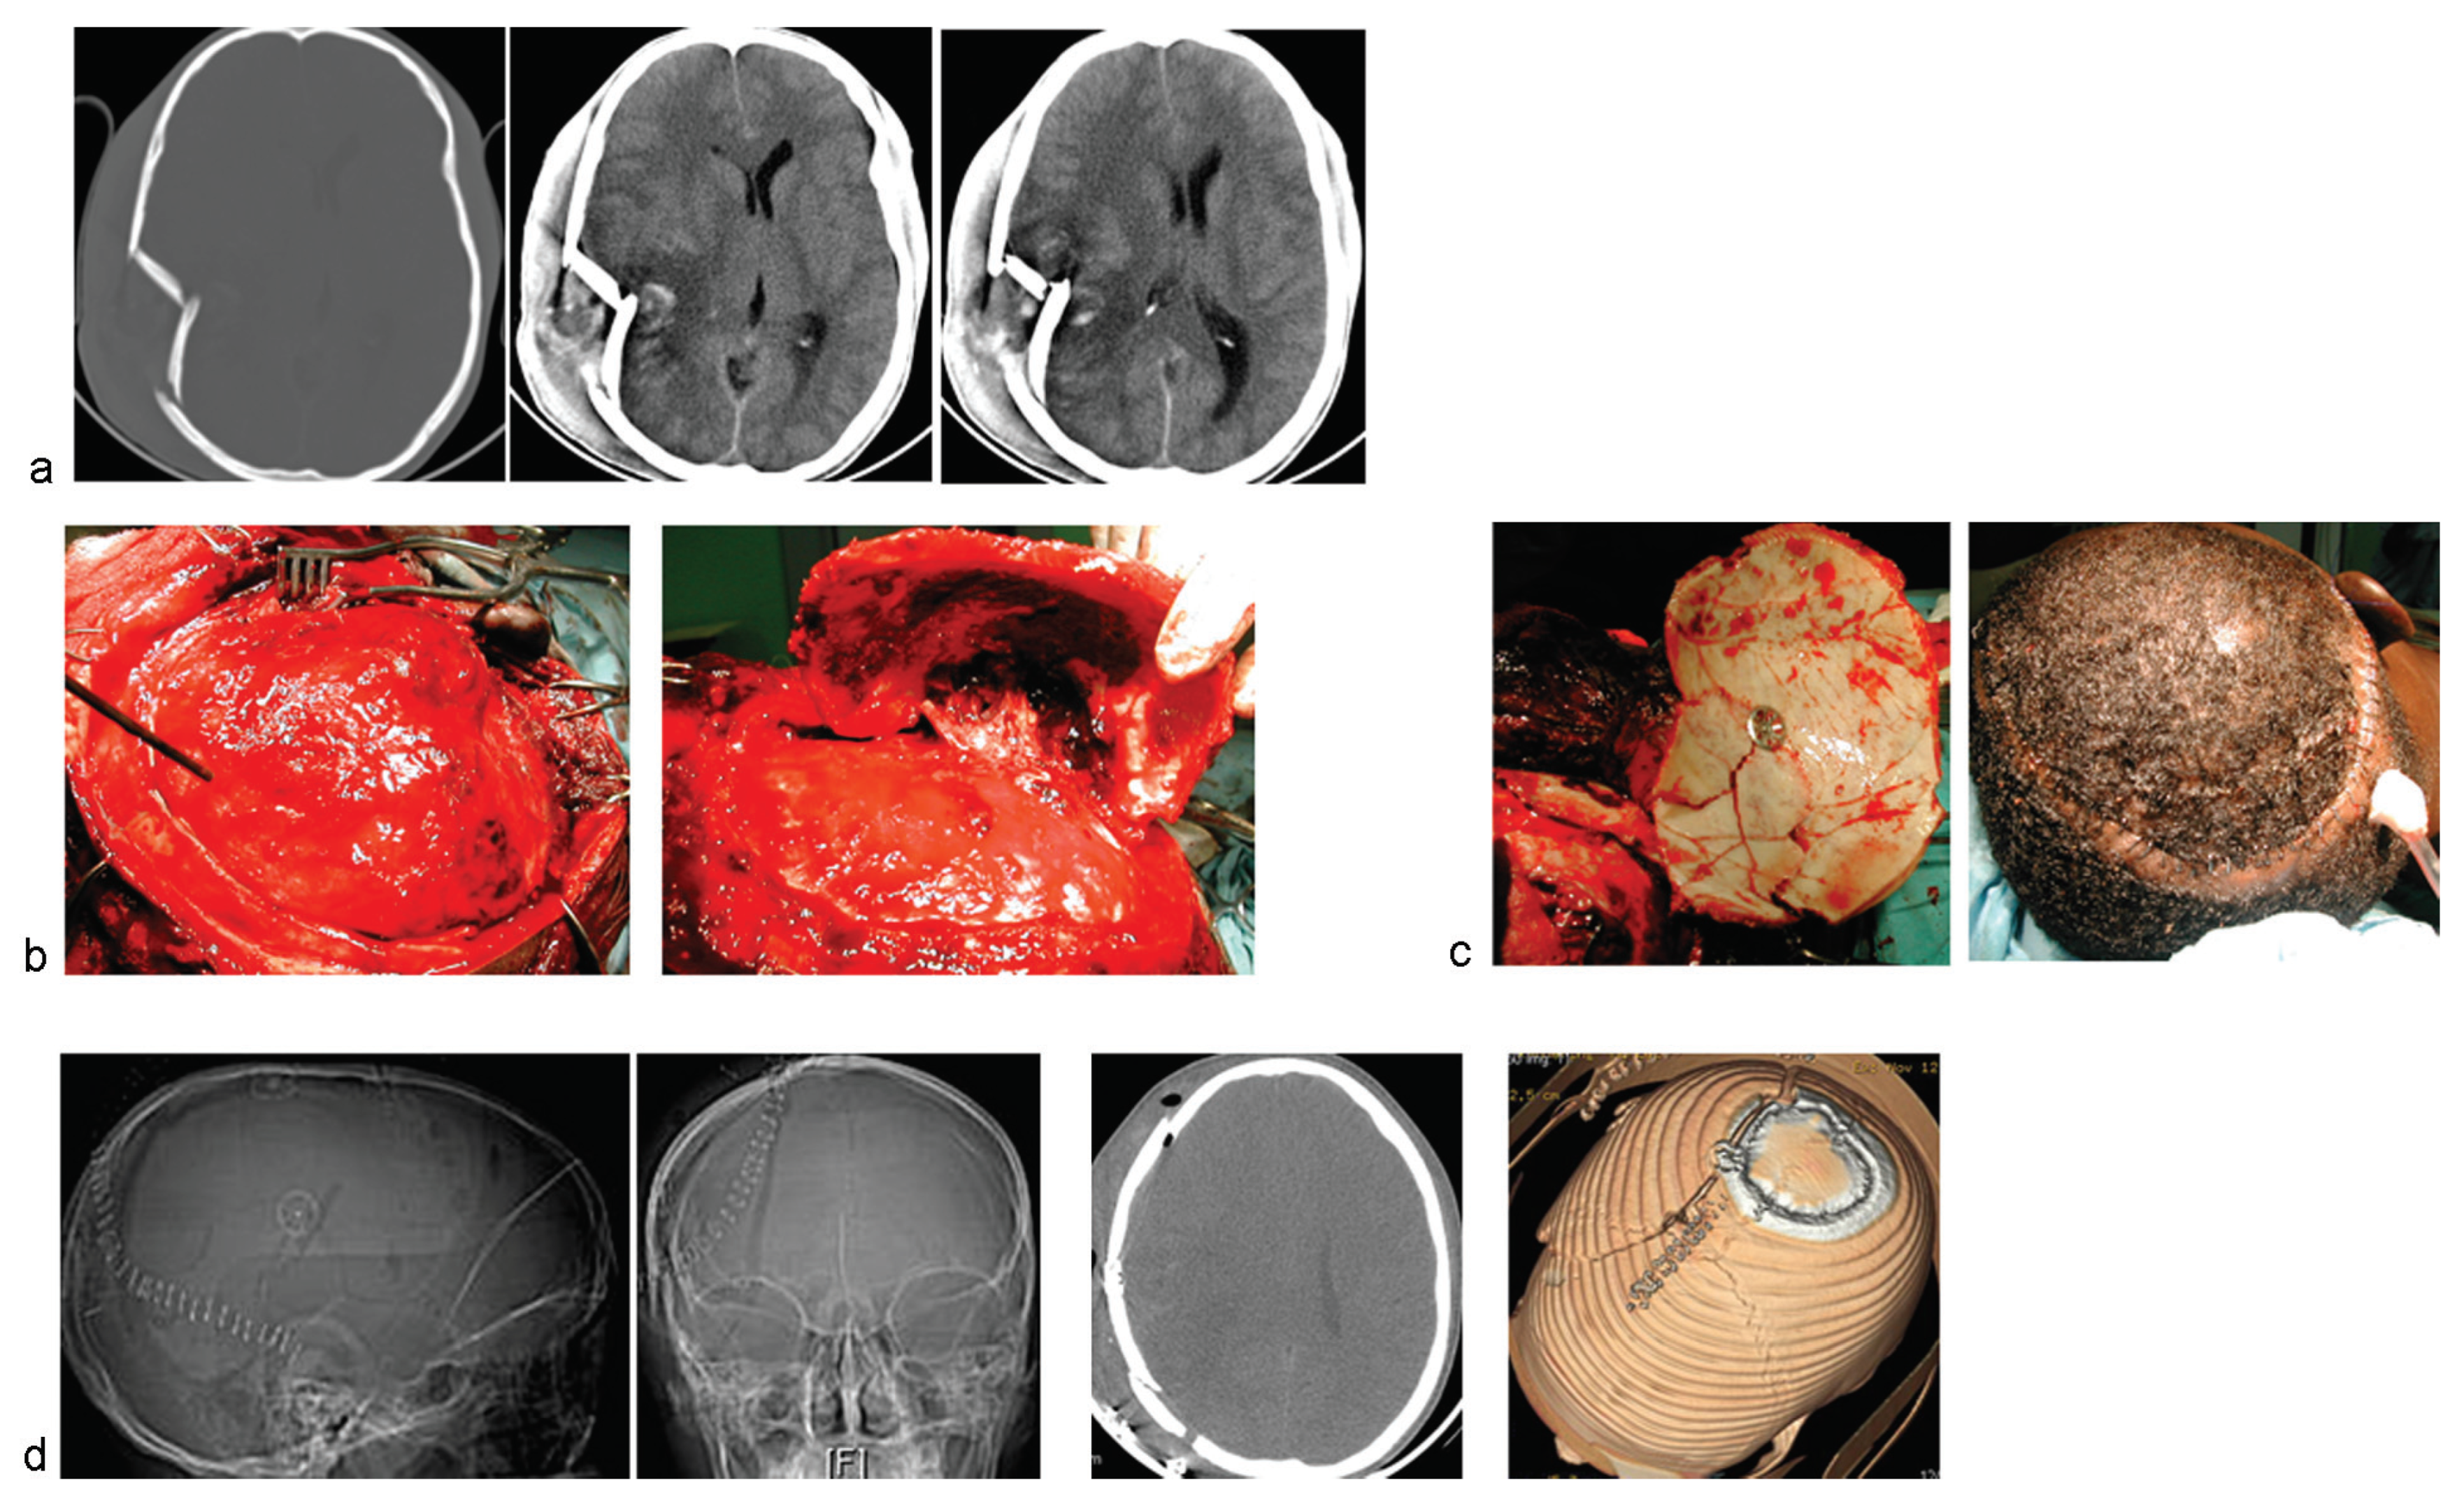

Figure 1,

Figure 2 and

Figure 3 illustrate the essential elements of the surgical steps for the use of the titanium clamps in this surgical procedure. First, standard scalp flaps (

Figure 1 and

Figure 2) or extension of overlying scalp lacerations (

Figure 3) are raised to expose the cranial-facial fracture lines. For elevation of the fracture fragments, attempts are made to achieve osteotomies and calvarial craniotomies that include intact bone segments to facilitate the reassembly of the fracture fragments (

Figure 2) [

Figure 2c) while other necessary intracranial work, extra- and/or intradural, is performed. The latter includes repair of dural tears and evacuation of traumatic brain lesions. Finally, the reassembling of the fragments is done, the aim always being autologous osteosynthesis. The bone fragments are brought on-site, sometimes actually force-impacted into position, and are held together by the titanium clamps. The latter are positioned between the bone fragments, and a single 16-mm CranioFix clamp is sometimes able to hold some four bone fragments together by so doing [